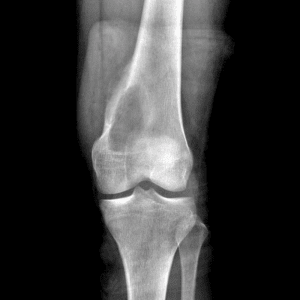

Pediatric Radiographs